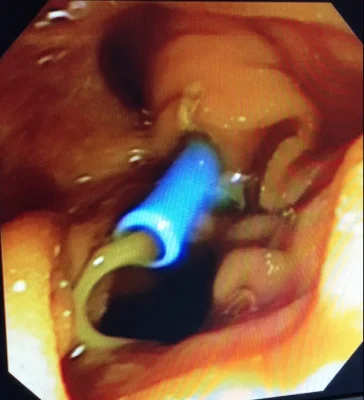

Colangioresonancia: este estudio permite evaluar la presencia de Cálculos en las vías biliares, esta condición corresponde a una enfermedad más compleja y requiere el drenaje de cálculos de la vía biliar adicionalmente a la Colecistectomía.